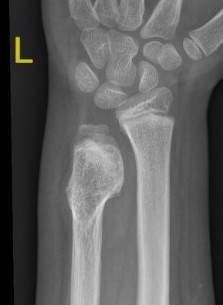

X-ray

Cortical and marrow continuity

1. Pedunculated - has a stalk, points away from joint

Pedunculated

Protuberant bony lesion arising adjacent to physis

- directed away from joint

- cortical bone and marrow space continuous

Ankle

Causes valgus deformity

- 19 patients with solitary osteochondroma of distal tibia or fibula

- cause plastic deformity and pronation deformity

- distal tibia more symptomatic than distal fibula